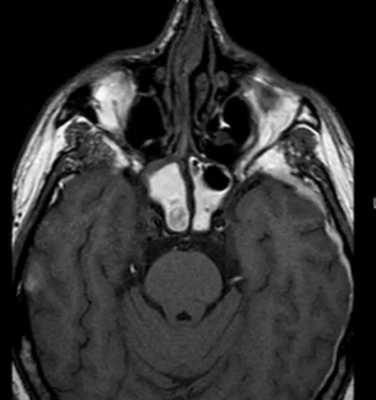

Двусторонний перелом мыщелковых отростков, гемартроз, изменения крыловидных мышц.

У пациентов с клиническими проявлениями внутренних нарушений ВНЧС ведущим методом лучевого исследования является функциональная МРТ. Наиболее информативными являются Pd- и Т2*-взвешенные изображения в кососагиттальных плоскостях.